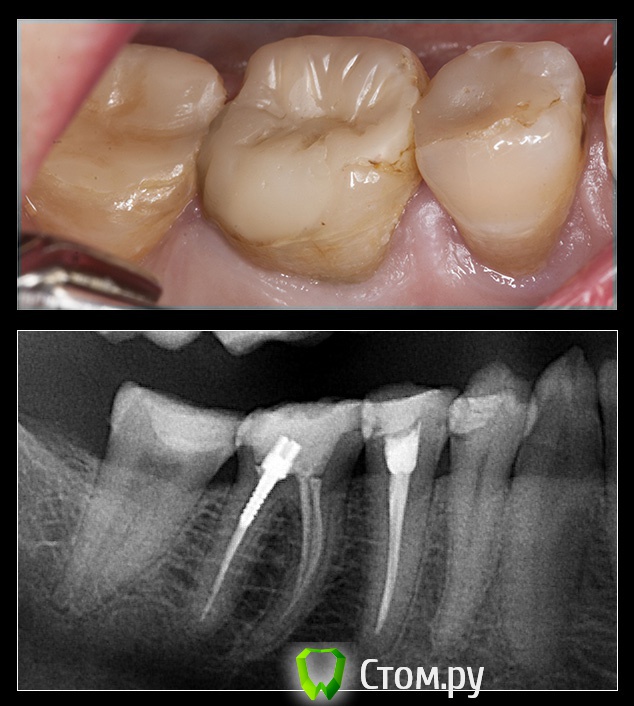

M@estro Опубликовано 14 сентября, 2014 Поделиться Опубликовано 14 сентября, 2014 (изменено) Эндо - ортопедический кейс. До вмешательства : http://s020.radikal.ru/i715/1409/ab/12f0b8206958.jpg 44 : http://s019.radikal.ru/i606/1409/ec/a20e5f3456a6.jpg в два этапа,язычный канал был обтурирован во второе посещение. Этот кейс был опубликован в группе "перелечивания и эндо". Латеральная конденсация. 45 : http://i077.radikal.ru/1409/ae/46e0381ae7eb.jpg Была положительная симптоматика ( перкуссия) , после лечения исчезла. "Patency" не получил. 46 : http://s018.radikal.ru/i520/1409/1a/57ad2b5a48aa.jpg тут стандартная "добыча" . 4.7 витальный. Ортопедия : http://s50.radikal.ru/i129/1409/b5/916fdb8a0ede.jpg http://s019.radikal.ru/i642/1409/82/4c4871c06c06.jpg http://s018.radikal.ru/i523/1409/76/4b62878e182a.jpg Такие дела . Изменено 14 сентября, 2014 пользователем M@estro 14 Ссылка на комментарий